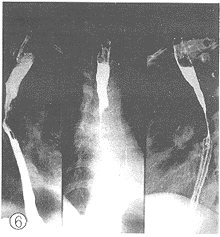

图7 食管中段癌髓质型

图8 放射治疗14d仍示病灶残留,病灶消退不足1/2。

2.1 X线影像比较:每例患者在术前加速放射治疗结束后第2d及第14d分别两次摄食管钡餐造影片。由放射科、放射治疗科、胸外科3名副主任医师以上的人员读片,读片前用胶布粘住每例患者的摄片的日期,再进行“多盲法”对比观察、记录。评判标准按1981年第三届全国放射学术会议(郑州)治疗组通过的食管癌放射治疗后X线诊断标准分为4级。Ⅰ级:病变完全消失,食管壁软而光滑,蠕动及扩张良好,粘膜纹理清楚可见(图1、 2);Ⅱ级:病变基本消失,食管壁规则,钡剂能顺利通过,但管壁仍僵直或狭窄,蠕动未恢复,粘膜仍增粗(图3、 4);Ⅲ级:病变明显好转,食管病灶退缩一半以上,没有明显扭曲、成角以及突出腔外的溃疡,稠的钡剂能通过(图5、 6);Ⅳ级:病变残留或恶化,病灶消退不到一半或成角,扭曲明显或有突出腔外的溃疡,钡剂通过极差(图7、 8)。118例术前加速放射治疗后不同时间的X线影像变化结果中,从Ⅲ、Ⅳ级病例上升为Ⅱ、Ⅲ级者最多,分别达 37.8%(17/45)和43.8%(7/16);但未发现越级上升和降级病例。